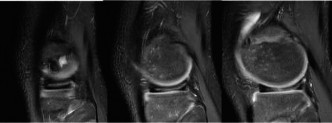

The MRI is obtained, and the patient returns with his parents to review the images (Figs. 10–27 and 10–28).

Figure 10–27

Figure 10–28 The diagnosis most consistent with the images shown in Figures 10–27 and 10–28 is:

The correct answer is (A). The patient has sustained an ACL tear. Once thought to be uncommon amongst pediatric populations, recent studies have shown these injuries are frequently encountered. A tibial eminence avulsion fracture is of concern in adolescent patients, though there is no evidence of injury at this location. The axial view of the patella shows no injury to the medial patellofemoral ligament or bone marrow edema at the patella or femoral trochlea which are signs of a possible patellar dislocation. The medial meniscus is intact.